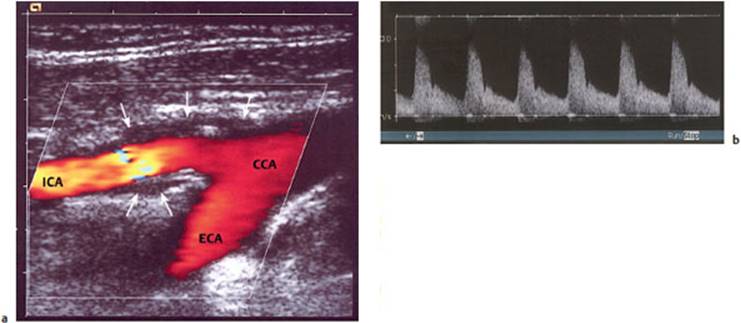

Fig. 4.26 Color-coded duplex ultrasonography of carotid stenosis. a Duplex ultrasonography of the carotid bifurcation. Rapid flow is coded as bright, slow flow as dark. Flow is abnormally rapid in the internal carotid a. (ICA) because the lumen is narrowed. Atherosclerosis can be seen in the thickened vessel wall (arrow). b Flow spectrum of the internal carotid a. showing elevated maximal systolic and end-diastolic velocities (from the laboratory of the Neurological and Neurosurgical Clinics, University of Berne, Switzerland). ECA = external carotid a., CCA = common carotid a.

Fig. 4.27 Color-coded duplex ultrasonography of an occlusion of the left internal carotid a. 3 cm above the carotid bifurcation. a Blood flow can be seen up to the bifurcation. In the internal carotid a. (ICALT), there is only minimal movement of the blood column. b Doppler ultrasonography reveals no more than a brief forward flow in early systole at greatly reduced maximal speed; backward flow is already seen in early diastole.

Fig. 4.27 c MR angiography reveals occlusion of the internal carotid artery.

Indications. The velocity and flow profile (laminar or turbulent) of the blood flowing within a particular vessel depend, among other things, on the vessel's caliber and on the nature of its wall. Ultrasound studies aid in the detection of vascular stenosis and occlusion, vessel wall irregularities, abnormalities of the speed and direction of blood flow, and turbulent flow. Insonation of the extra- and intracranial vessels (e.g., of the middle cerebral a. through the thin bone of the “temporal window,” or of the basilar a. through the foramen magnum) yields an informative picture of the current state of blood flow in the brain (Fig. 4.27). This diagnostic technique is inexpensive, non-invasive, and free of risk.